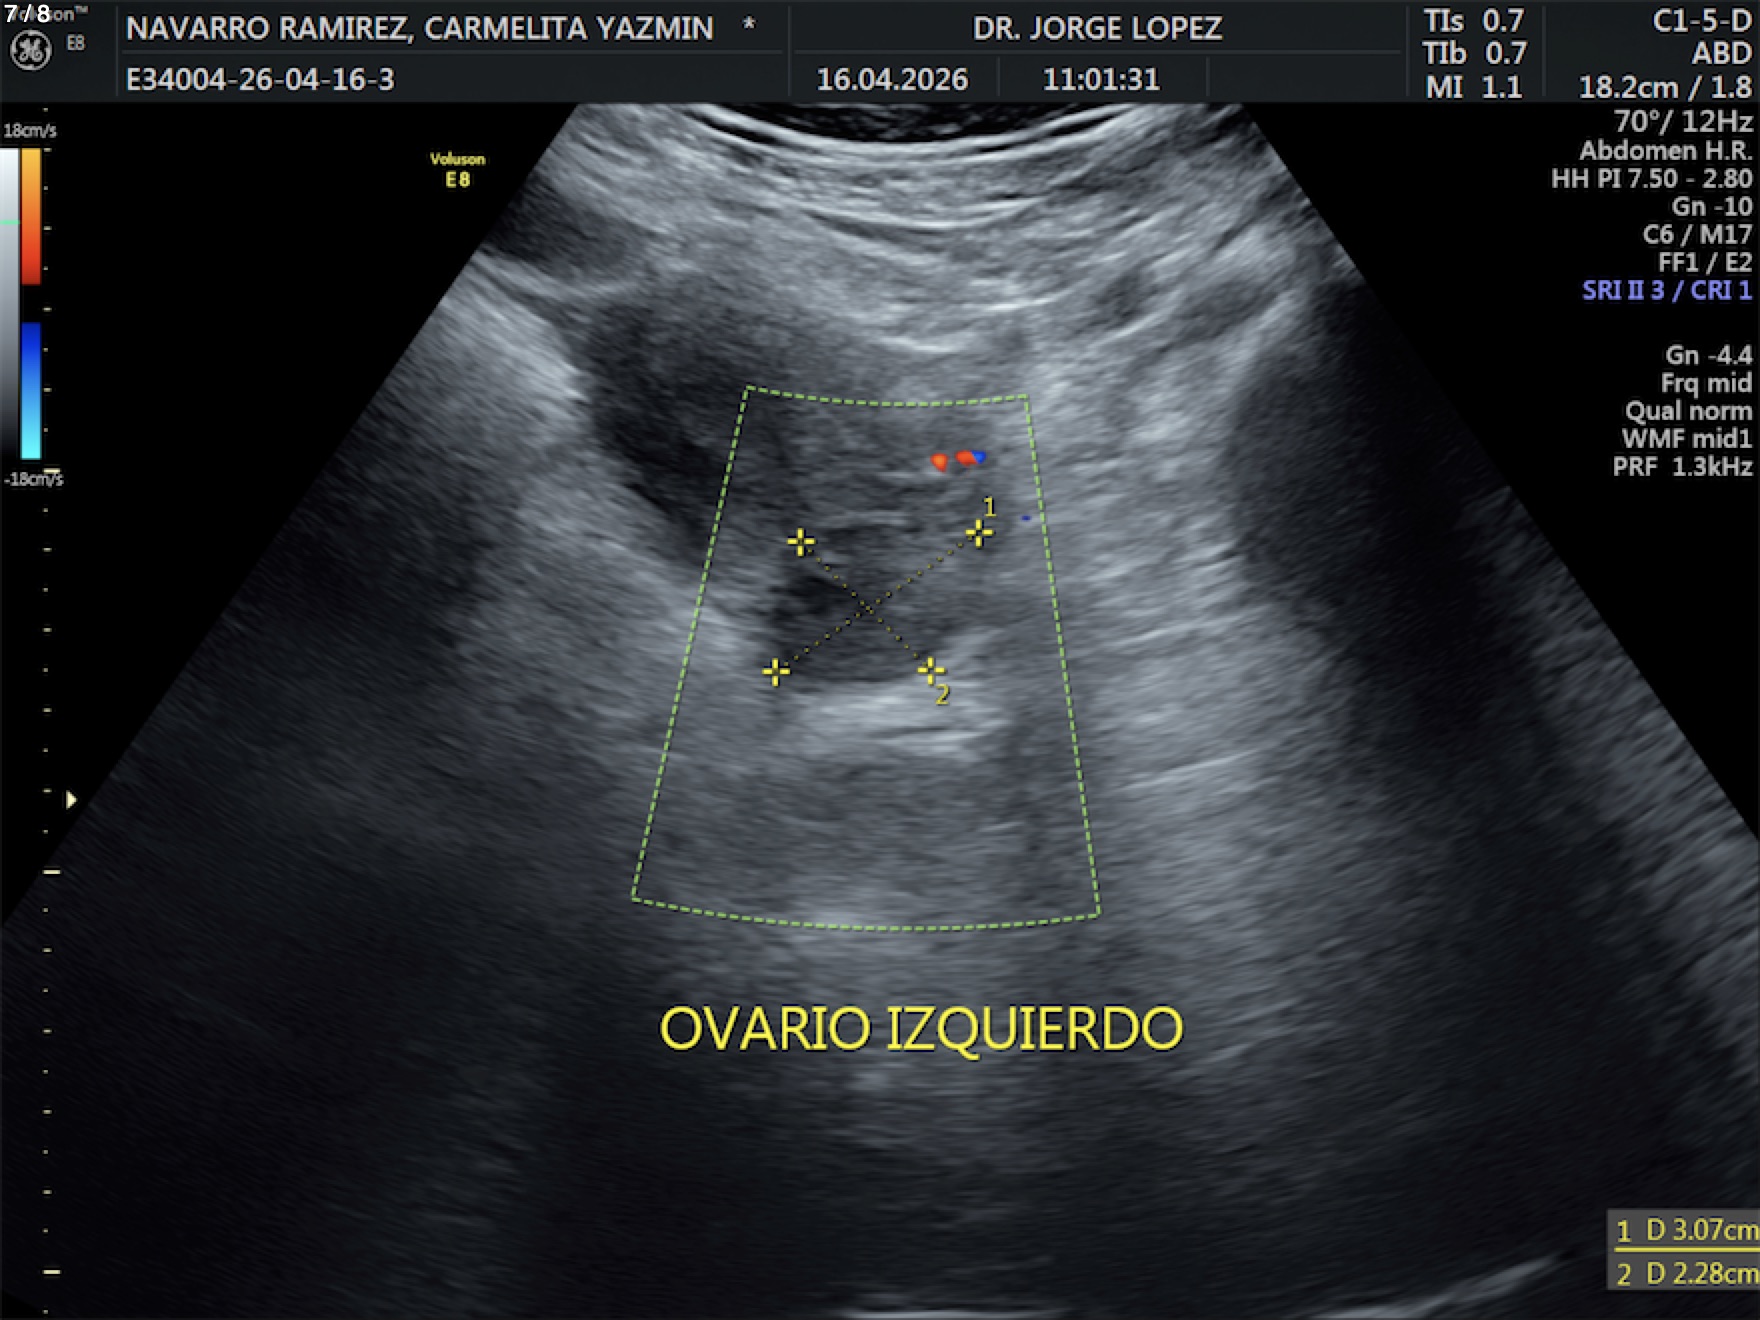

Navarro Ramirez Carmelita Yazmin - Unnamed